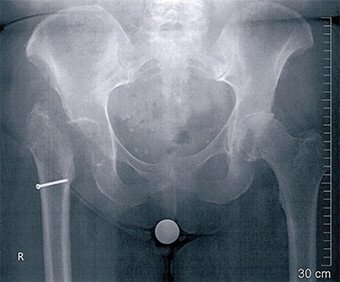

Die klinische Untersuchung und das Röntgenbild zeigten einen spontanen Abriss der Hüftmuskulatur, der sich im Magnetresonanz-Tomogramm bestätigte. Diese Befunde konnten auch bei der Operation verifiziert werden. Der Hüftmuskel war zu 90 Prozent abgerissen und aufgrund Nichtgebrauchs teilweise verfettet. Der Muskel wurde mit starken Fäden wieder an den Knochen angenäht und die Nähte zusätzlich über eine Schraube gesichert. Damit die Muskulatur spannungsfrei anheilen konnte, wurde jeweils der Hüftkopf entfernt. Dies führte zu einer Gehunfähigkeit, weshalb die Patientin die meiste Zeit bis zur Reoperation in einem Rollstuhl verbringen musste.